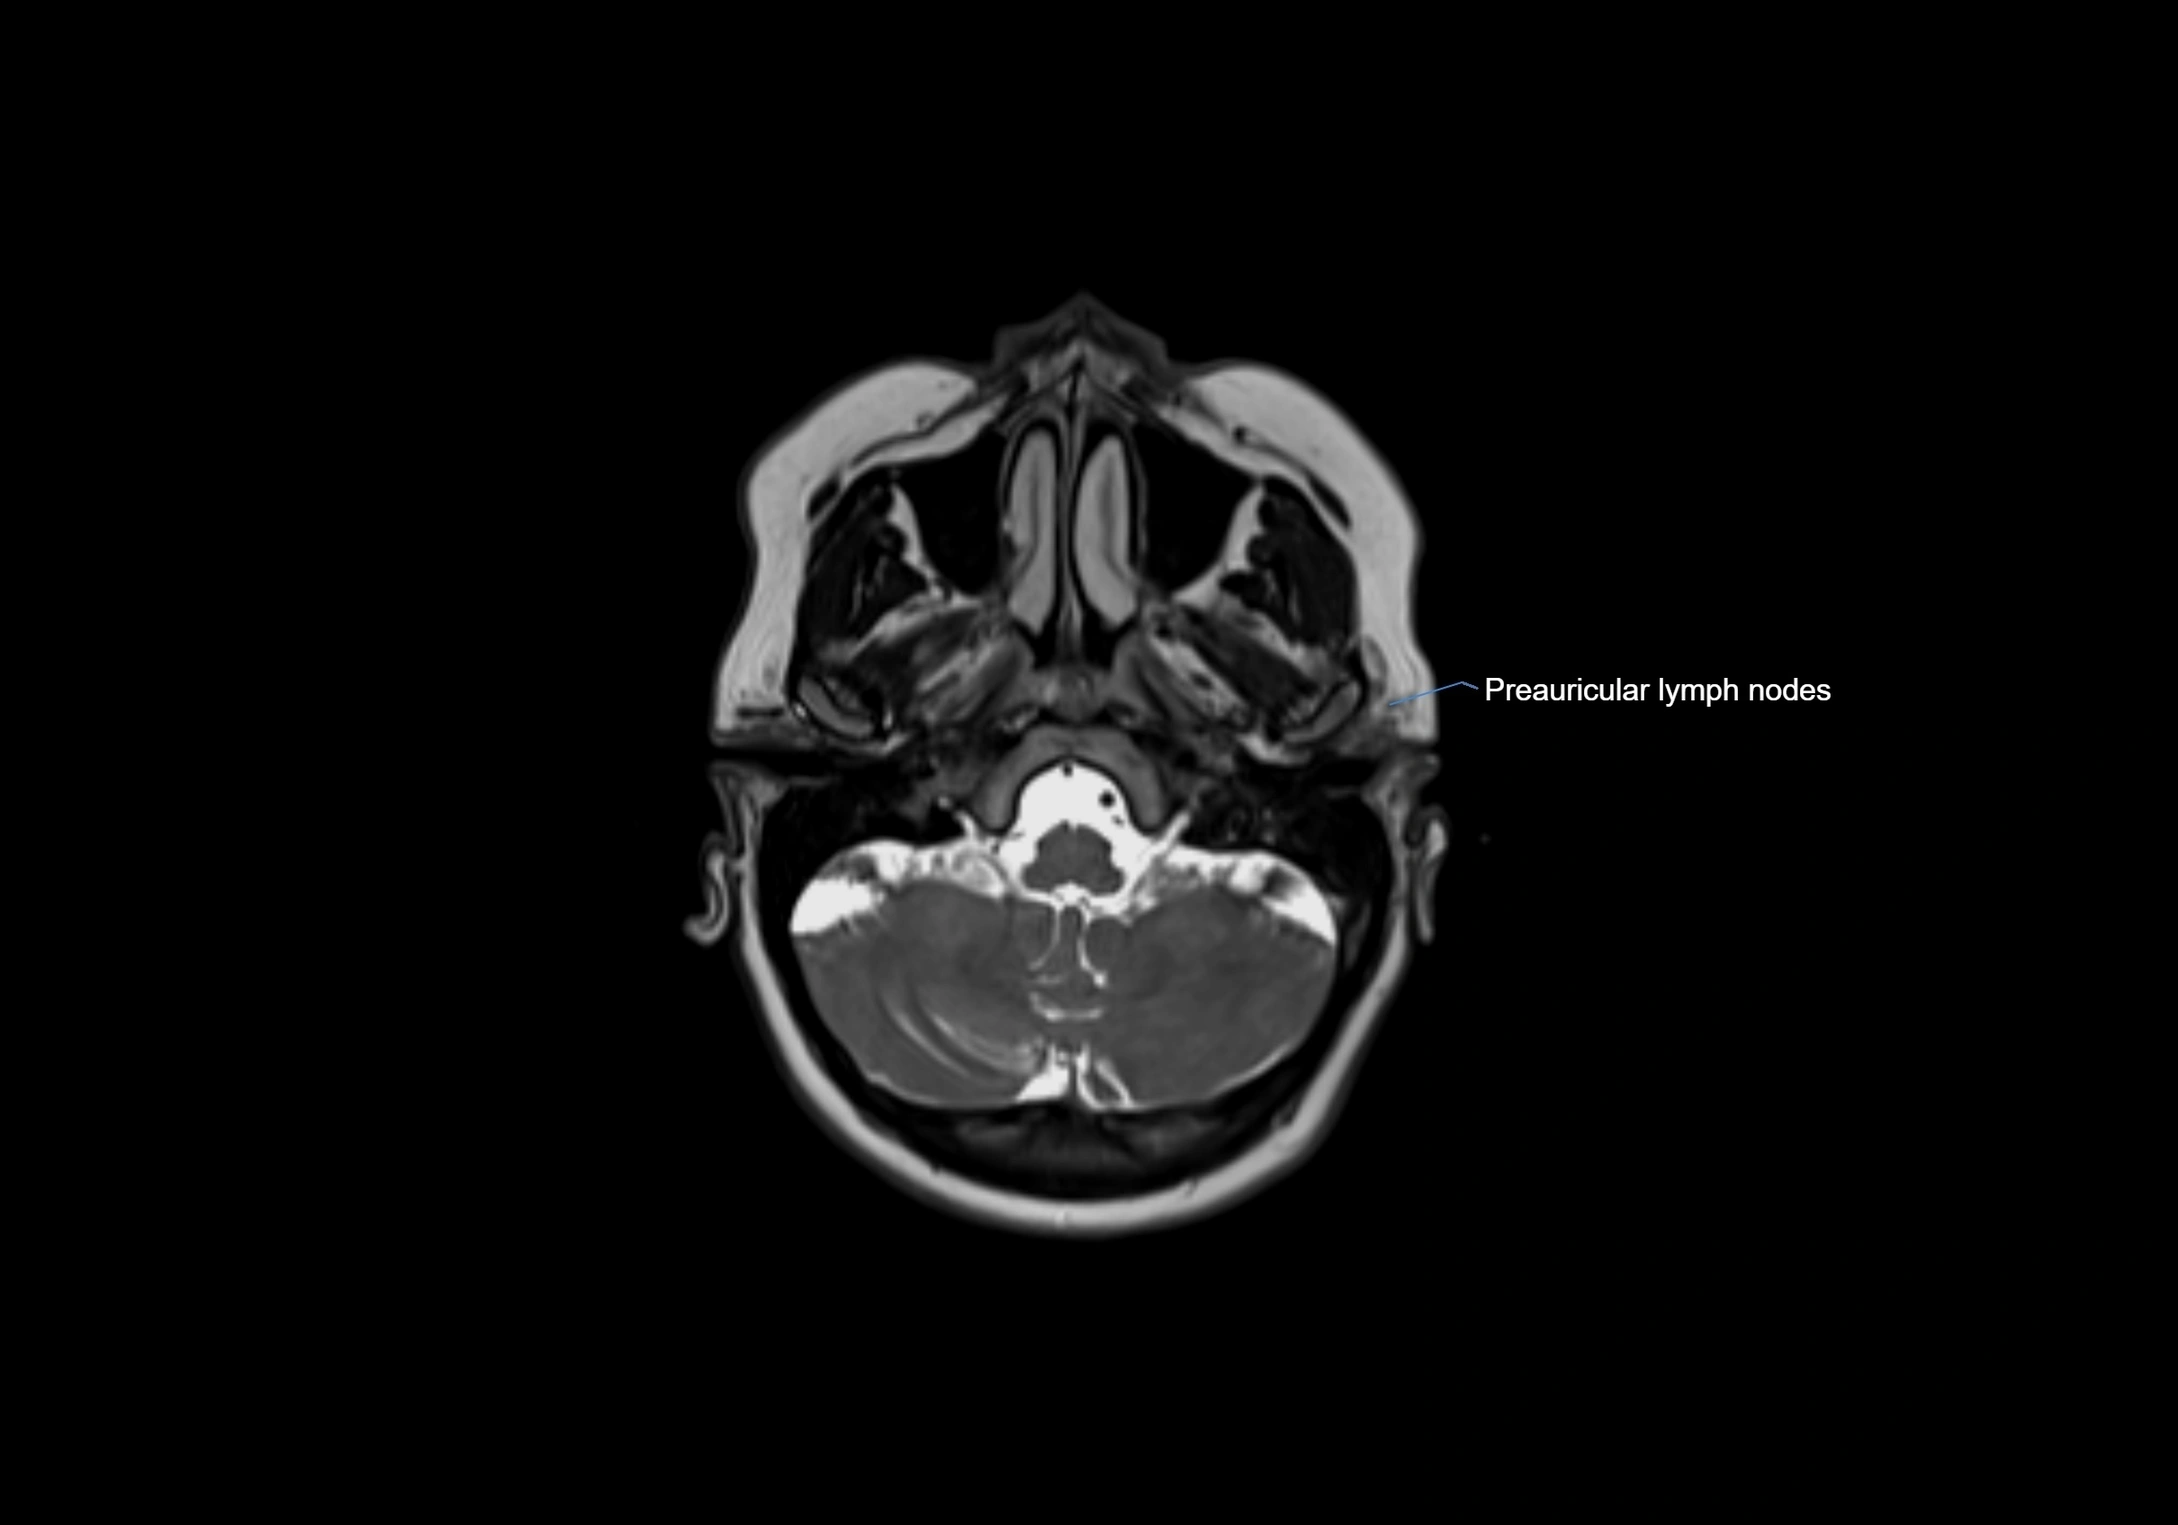

Accessory lymph nodes are small, secondary lymph nodes located along the main facial and cervical lymphatic chains, often adjacent to primary lymph nodes, such as preauricular, submandibular, or occipital nodes. They are typically less than 5 mm in diameter, embedded within subcutaneous fat or connective tissue, and may be variable in number and location. These nodes provide additional filtration and immune surveillance for lymph collected from the face, scalp, and neck regions. Accessory lymph nodes are usually non-palpable in healthy individuals but may enlarge in response to infection, inflammation, or metastasis, making them clinically significant.

• Found along primary lymph node chains, including preauricular, submandibular, parotid, and occipital regions

• Embedded in subcutaneous fat or superficial fascia, often lateral or posterior to primary nodes